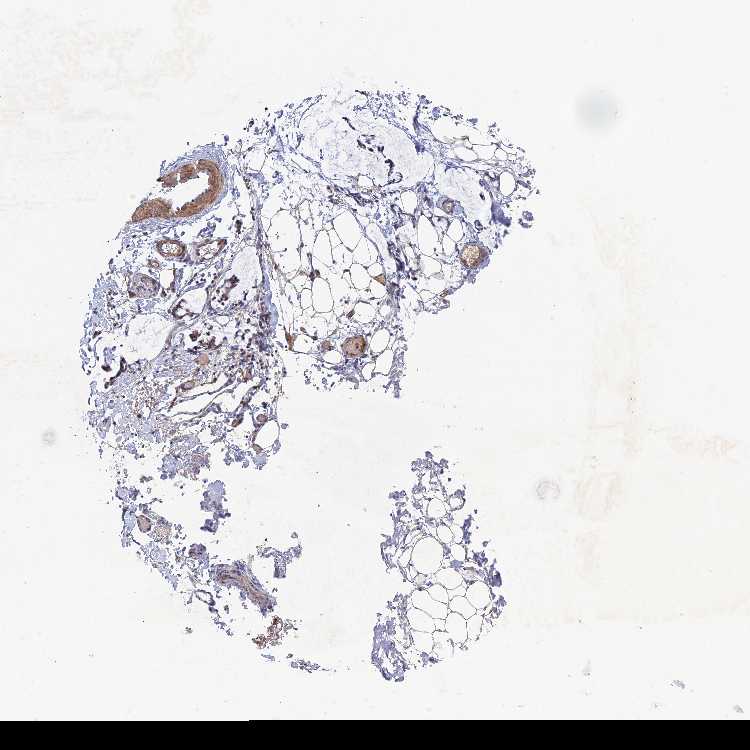

SOFT TISSUE 1 - Antibody stainingi

Antibody staining in the annotated cell types in the current human tissue is reported as not detected, low, medium, or high, based on conventional immunohistochemistry profiling in selected tissues. This score is based on the combination of the staining intensity and fraction of stained cells.

Each image is clickable and will lead to virtual microscopy that enables deeper exploration of all samples and also displays staining intensity scores, fraction scores and subcellular localization as well as patient and tissue information for each sample.

Antibody HPA039613

Chondrocytes Not detected

Fibroblasts Not detected

SOFT TISSUE 2 - Antibody stainingi

Peripheral nerve Low